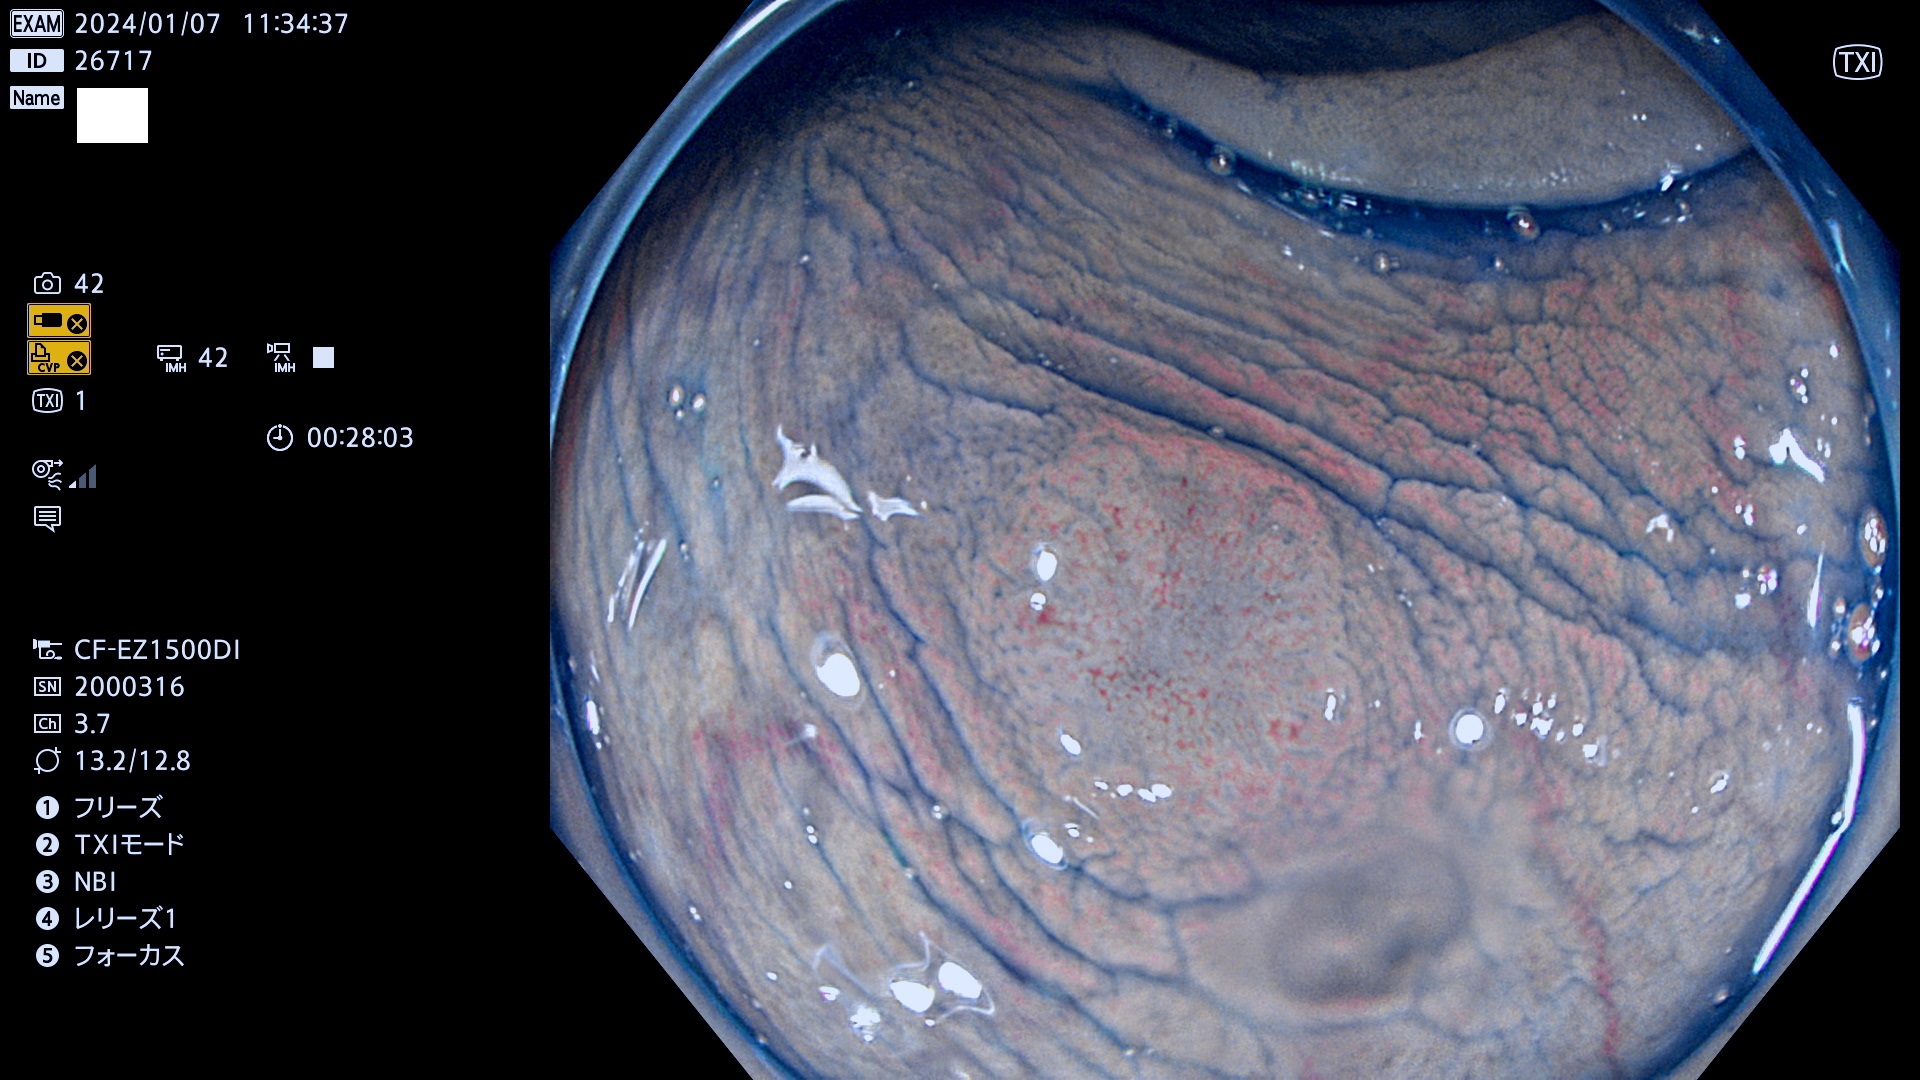

表面型腺腫(Flat Adenoma)の中で、完全に平坦な物をUb、陥凹している物をUcと呼びます。平坦隆起型(Ua)よりも、発見が難しく危険な病変です。

毎週の検査(木・金・土・日)に発見されたUb、Uc型・腺腫を、その週の日曜の夜にUPし1週間、提示します。

抽出の対象期間 2024年1月6日(土)〜1月8(月)の4日間(34件の検査)7件